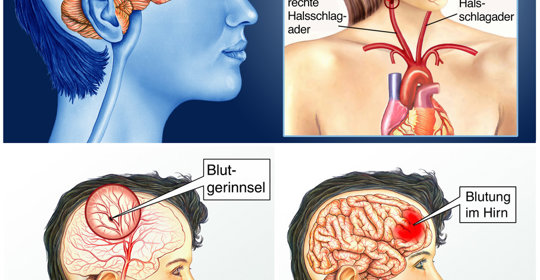

腦中風後遺症的症狀、前兆、治療和預防

腦溢血後遺症的症狀、前兆、治療和預防

腦血管破裂後遺症的症狀、前兆、治療和預防

腦梗塞後遺症的症狀、前兆、治療與預防

腦栓塞後遺症的症狀表現、前兆、治療與預防